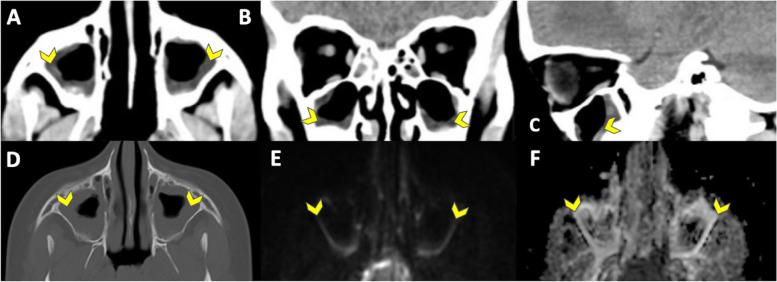

Brain CT can be used to evaluate pediatric patients with suspicion of cerebral pathology when anesthetic and MRI resources are scarce. This study aimed to assess if pediatric patients referred for an elective brain CT could endure a diagnostic fast brain MRI without general anesthesia using a one-minute multi-contrast EPI-based sequence (EPIMix) with comparable diagnostic performance.

Pediatric patients referred for an elective brain CT between March 2019 and March 2020 were prospectively included and underwent EPIMix without general anesthesia in addition to CT. Three readers (R1-3) independently evaluated EPIMix and CT images on two separate occasions. The two main study outcomes were the tolerance to undergo an EPIMix scan without general anesthesia and its performance to classify a scan as normal or abnormal. Secondary outcomes were assessment of disease category, incidental findings, diagnostic image quality, diagnostic confidence, and image artifacts. Further, a side-by-side evaluation of EPIMix and CT was performed. The signal-to-noise ratio (SNR) was calculated for EPIMix on T1-weighted, T2-weighted, and ADC images. Descriptive statistics, Fisher's exact test, and Chi-squared test were used to compare the two imaging modalities.

EPIMix was well tolerated by all included patients (n = 15) aged 5-16 (mean 11, SD 3) years old. Thirteen cases on EPIMix and twelve cases on CT were classified as normal by all readers (R1-3), while two cases on EPIMix and three cases on CT were classified as abnormal by one reader (R1), (R1-3, p = 1.00). There was no evidence of a difference in diagnostic confidence, image quality, or the presence of motion artifacts between EPIMix and CT (R1-3, p ≥ 0.10). Side-by-side evaluation (R2 + R4 + R5) reviewed all scans as lacking significant pathological findings on EPIMix and CT images.

Full brain MRI-based EPIMix sequence was well tolerated without general anesthesia with a diagnostic performance comparable to CT in elective pediatric patients.